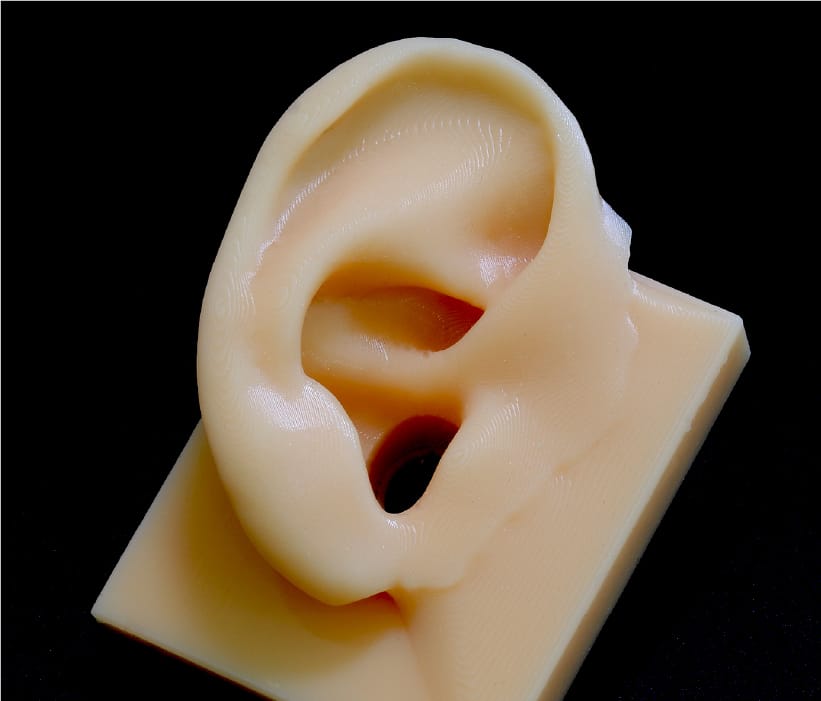

Soft model with unique technology

In general, soft models often fail to reproduce some shapes, such as simplifying the inside of organs, but JMC Lab possesses a unique technology that combines 3D printing and casting technologies to faithfully reproduce the outside and inside of organs. JMC Lab has a unique technology that combines 3D printing and casting techniques to faithfully reproduce the outside and inside of organs. This method allows for a higher degree of material flexibility than direct 3D printing of soft materials, and allows for adjustments in hardness, color, X-ray transmission, etc.

Soft organ model

One of the strengths of JMC's medical entity models is the ability to produce soft models. However, JMC's unique know-how and painstaking manufacturing methods enable us to accurately reproduce the complex shapes of organs and to adjust the hardness according to the part to be manufactured. JMC's unique know-how and labor-intensive manufacturing methods enable us to accurately reproduce the complex shapes of organs and adjust the hardness of the parts we manufacture.